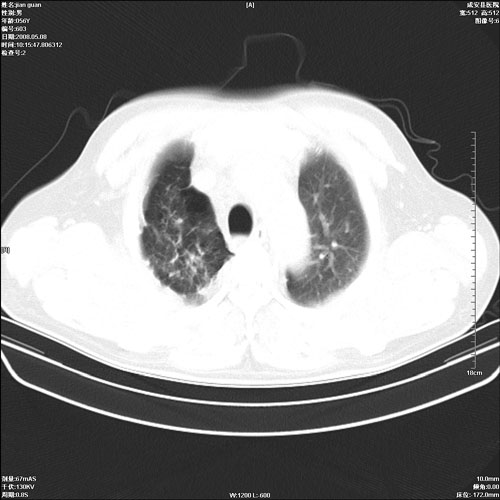

病人 男 60岁 主诉 胸闷 无明显发热 一般情况尚可。

两上肺陈旧性结核;慢支肺气肿、伴感染?

两上肺陈旧性结核;慢支肺气肿

1.两上肺陈旧性结核;慢支肺气肿。

两上肺陈旧性结核,慢支肺气肿。

两上肺陈旧性结核;慢支肺气肿。肺肺间质纤维化

两上肺陈旧性结核;慢支肺气肿。